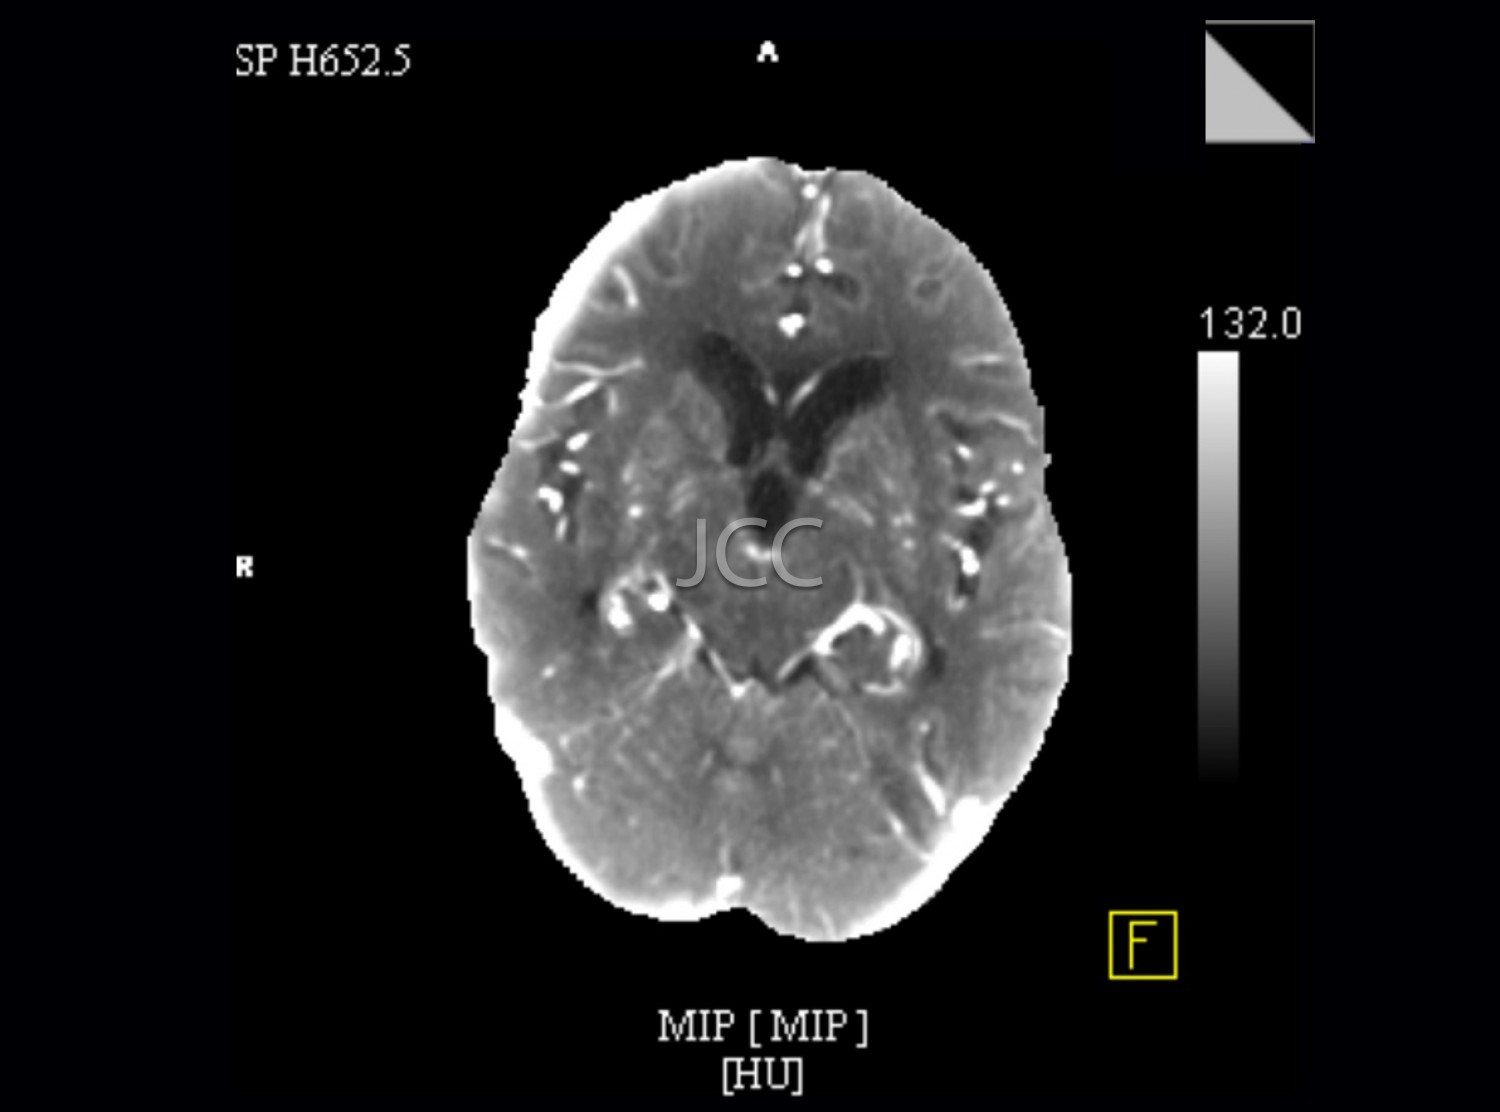

Discover here the exams available in the clinics of the Dr. João Carlos Costa Group.